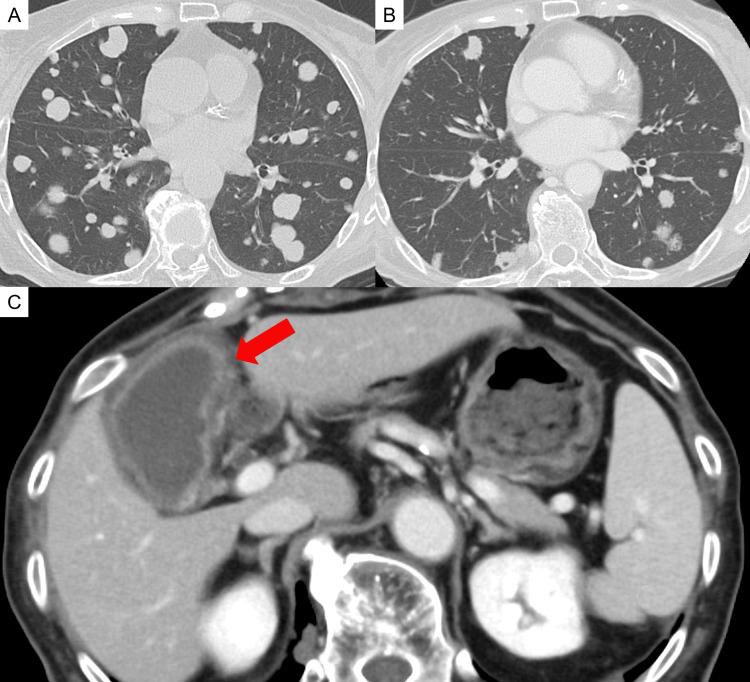

前上纵隔原发性腺样囊性癌(ACC)在临床实践中很少见,目前尚未确立标准治疗方案。我们对一名以呼吸窘迫为主要症状的纵隔原发性ACC患者进行了姑息性放疗,以改善气道狭窄。放疗后,ACC体积缩小,因ACC压迫导致的狭窄气道得以开通,患者的一般状况有所改善。我们报告该病例的结果并复习相关文献。